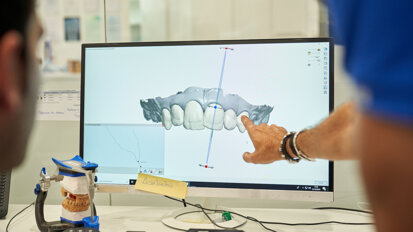

Digital Smile Desig (DSD) to praktyczne cyfrowe narządzie wspomagające stomatologiczne leczenie estetyczne. Przystępny protokół umożliwia ...

Digital Smile Desig (DSD) to praktyczne cyfrowe narządzie wspomagające stomatologiczne leczenie estetyczne. Przystępny protokół umożliwia ...